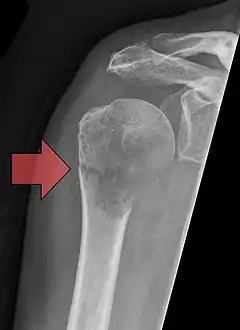

![]() كسر مرضي في العضد كسر مرضي في العضد | |